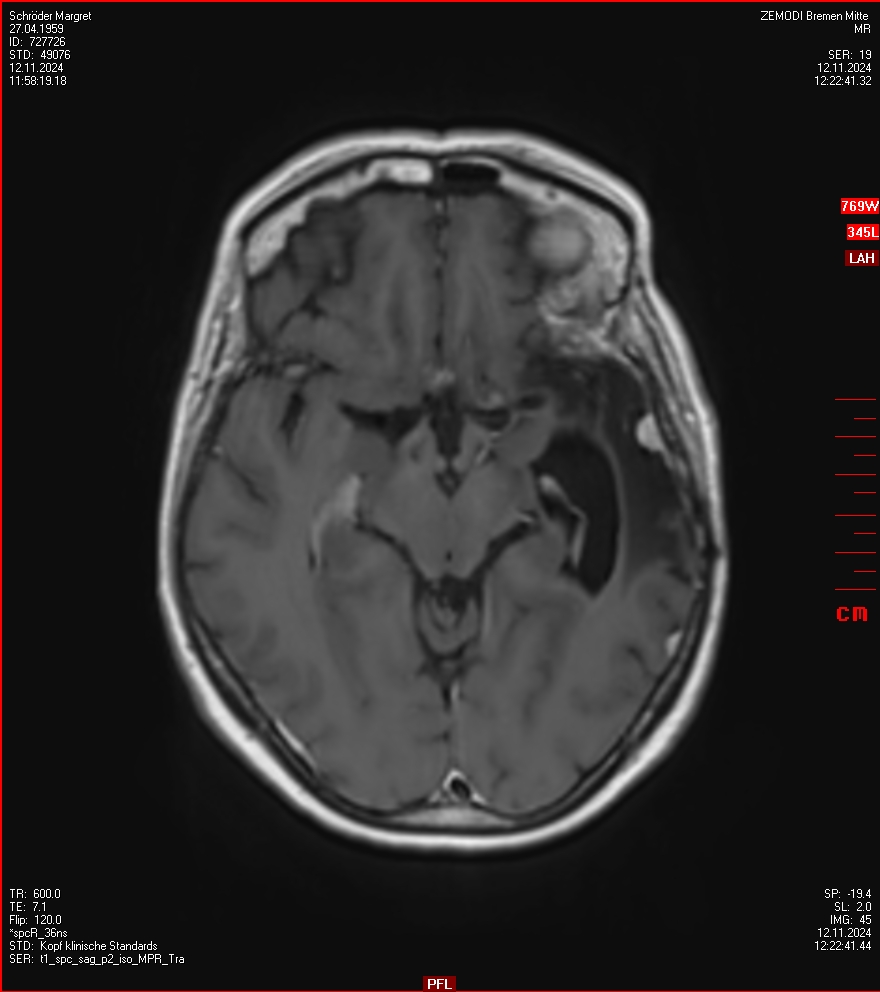

MRT vom 12. November 2024

So nun ein paar neue Bilder aus meinem Kopf. (Durch klicken bekommt man eine größe Ansicht eines Einzelbildes).

Die letzten drei Bilder Zeigen aus meiner Sicht den Tumor, der im Jahr 2021 bestrahlt wurde.

Ich denke, in den letzen 12 Monaten sind da ein paar Rezidive gewachsen,  vor 12 Monaten waren sie auch schon zu erkennen - vorher noch nicht. Nun hoffe ich auf den Rat des Spezialisten. Hoffendlich kann man etwas machen.